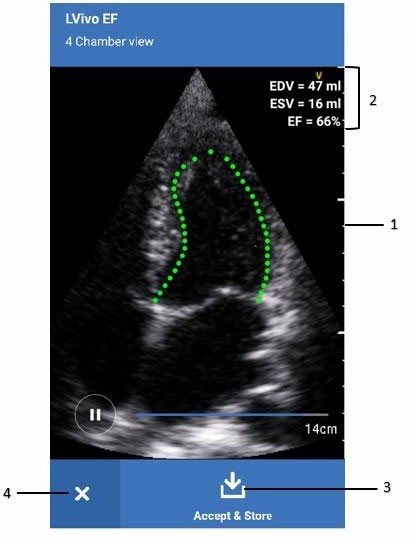

LVivo EF measurement

- Border

- Measurement results

- Accept & Store button

- Close button

5. LVivo EF app automatically traces the LV contours and draws a border around it.

6. End-Diastolic Volume (EDV), End-Systolic Volume (ESV) and Ejection Fraction (EF) values are calculated and displayed on the screen.

7. Press “Accept and store” to save the cine clip with measurement results.

8. Press Close button to quit LVivo EF app.